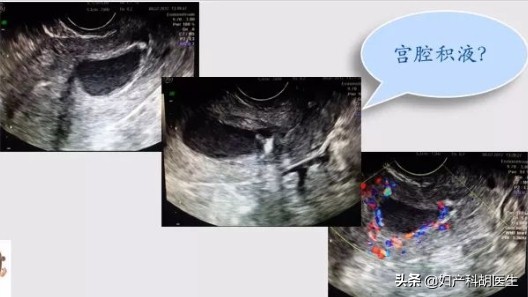

什么是宫腔积液?

宫腔积液,顾名思义,就是是指子宫腔内有液体积聚,那么积聚的液体就可能是积水、积血或者积脓。有宫腔积液不代表一定是生病了,可能是生理性的,也可能性是病理性的。